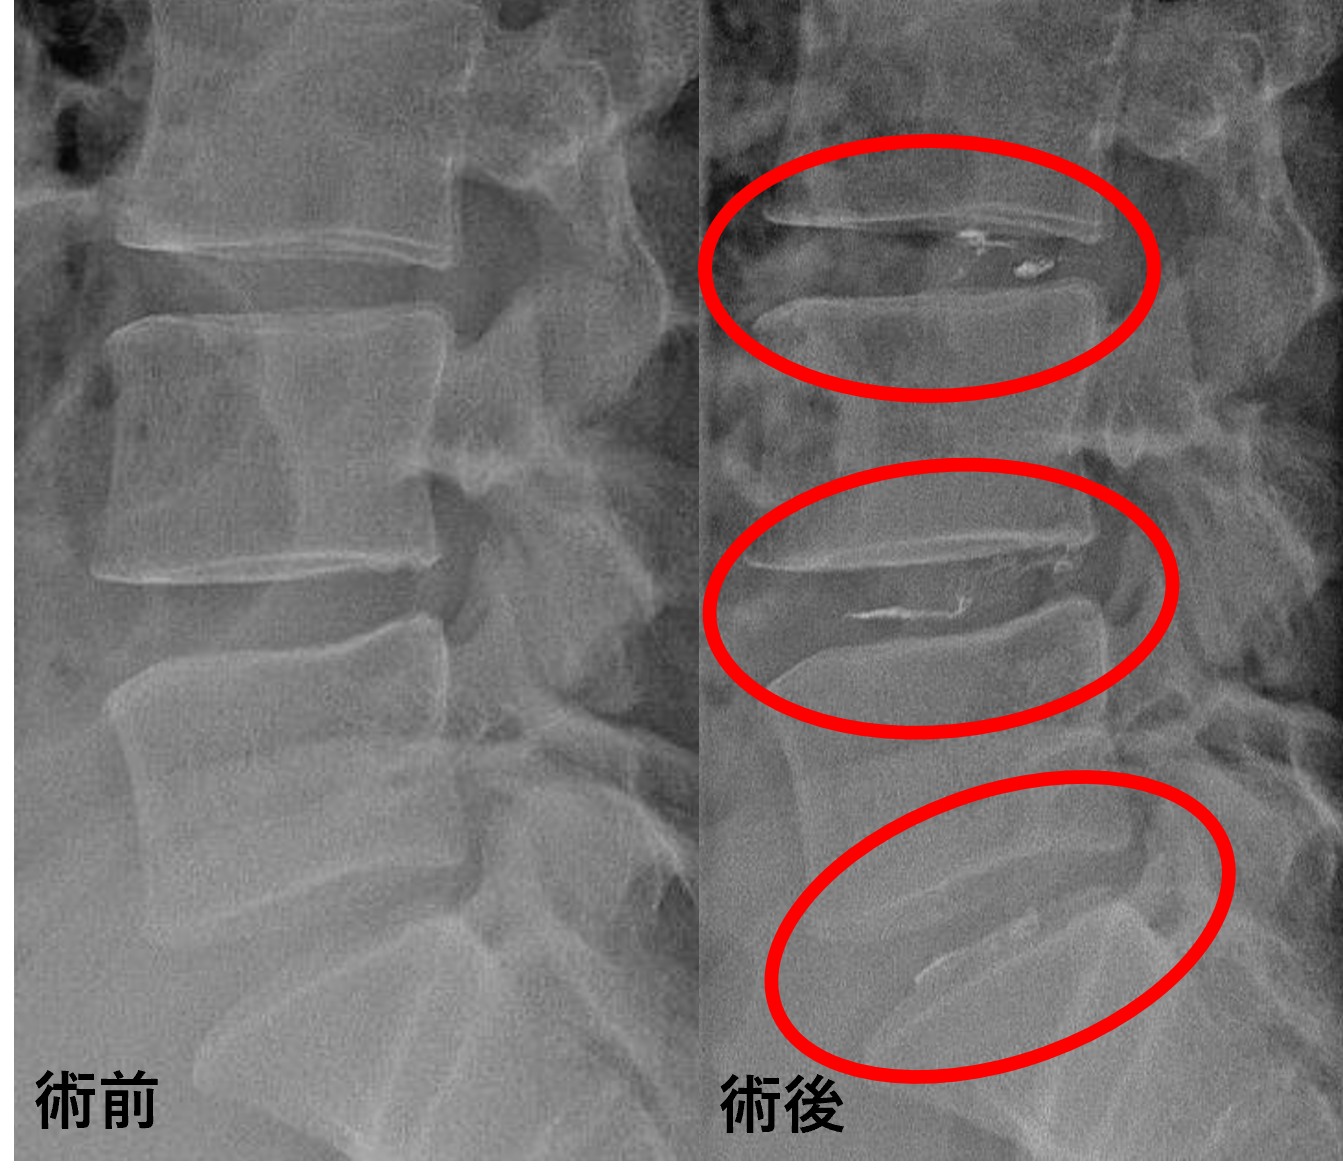

画像及び所見にについて

- L3/4 – 椎間板変性、膨隆

- L4/5 – 椎間板変性、膨隆、繊維輪断裂

- L5/s – 椎間板変性、椎間板ヘルニア

以上のことが画像上認められました。

L3/4、4/5、5/sの椎間板所見による脊柱管の圧排が、症状の原因の可能性が高い。

患者様と相談の元、L3/4、4/5、5/sにセルゲル法を施行